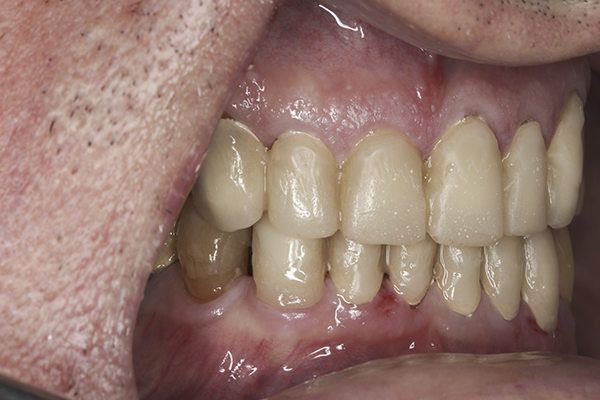

(9.) Preoperative right lateral, closed view.

Figure 9

(10.) Preoperative anterior, closed view. Note the end-to-end occlusion of the anterior teeth and the wear on the incisors and centrals resulting in no anterior or canine guidance.